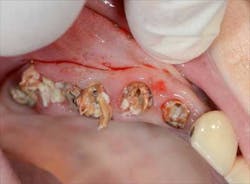

Fig. 2: Remaining teeth in the upper right

Mandibular arch: the lower jaw is fully edentulous. Initially, according to the patient, an implant-supported five-unit bridge (23 to 27) was made on four implants (Alphabio®) placed in 2007. Tooth 22 was present at the time and a removable partial denture replaced the bilateral posterior missing teeth.

Then, in January 2012, tooth 22 was extracted and a second implant specialist placed a new implant (Zimmer Dental®) to replace it. The GP decided to use a Locator® attachment system on this new implant and have the existing denture stabilized over it, without paying any attention to the collapsing situation of the upper right.Fig. 3: CT scan shows the existing implants positions and the bone volume available

A few months after this treatment phase, the patient is still unable to chew comfortably. The lower denture is now hurting and she notes a bad odor coming out of the now moving upper right teeth. Even more sadly, she can’t find a dentist able to get her out of trouble.